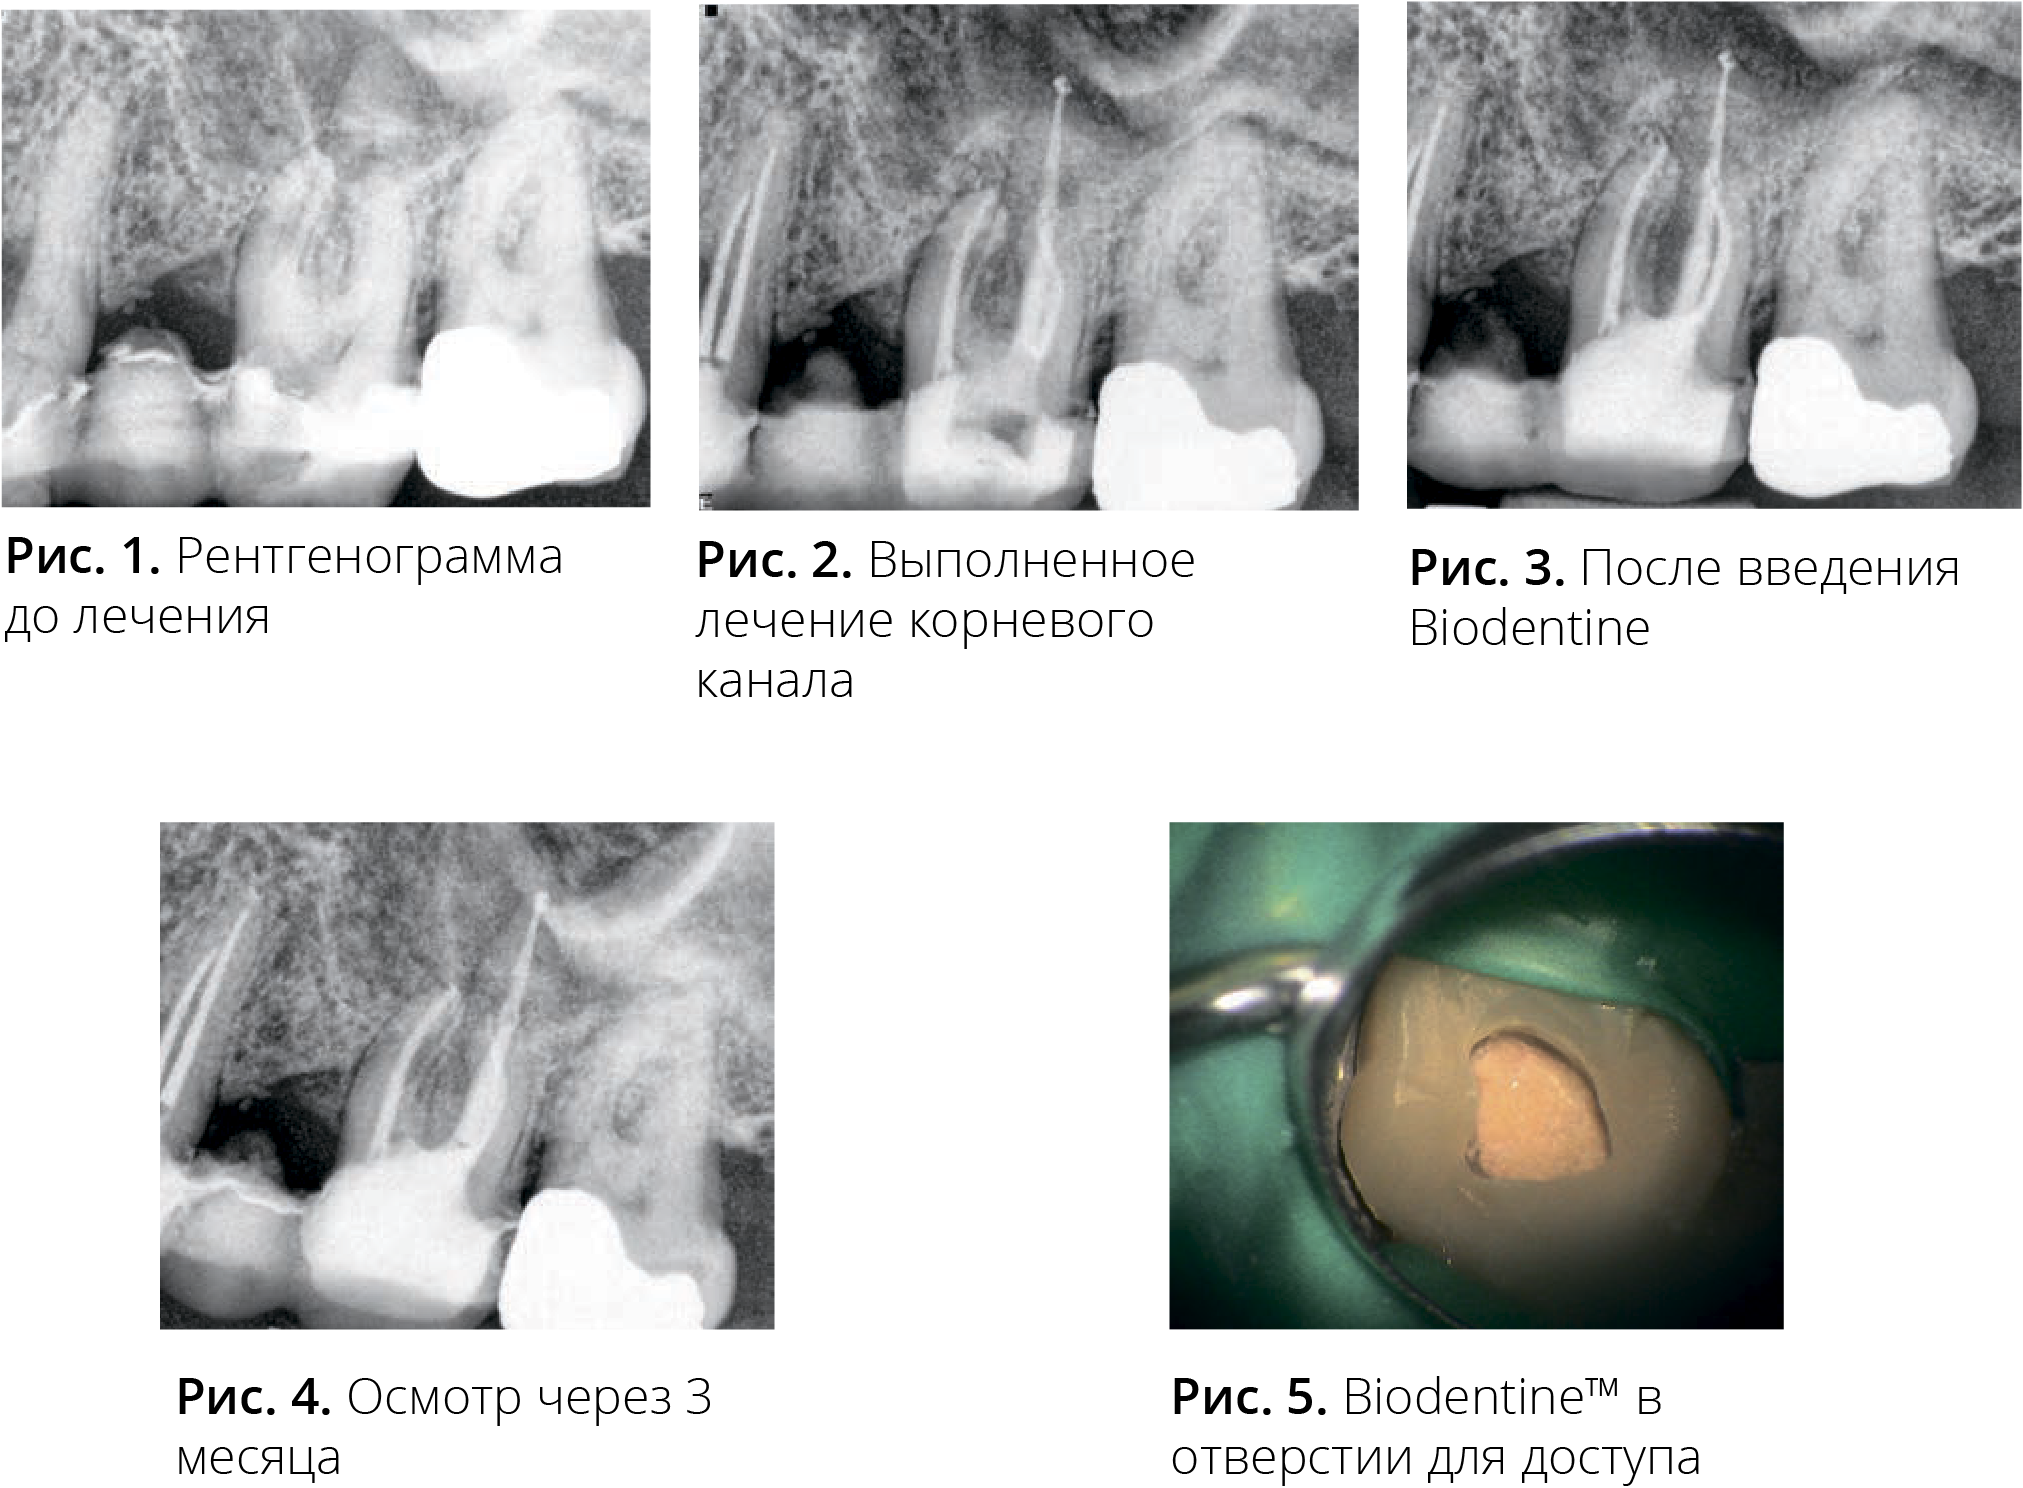

Случай № 1. Пациент – 49-летний мужчина

Первую эндодонтическую процедуру выполнили в зубе 26.

Зуб изолировали коффердамом, и в течение всего процесса лечения использовали операционный микроскоп. Рабочую длину установили с помощью апекс-локатора, а каналы обработали инструментами RaCe Ni-Ti в соответствии с ISO 35, конусность – 0,04.

Для ирригации использовали 3% р-р NaOCl, 17% ЭДТК и пассивную ультразвуковую ирригацию (ПУИ) Irrisafe. Пломбирование осуществляли с помощью силера Kerr RC GP SystemB и Obtura. Было обнаружено, что дно пульповой камеры имело ненормальный сотообразный вид. Отверстие для доступа восстановили с помощью СИЦ. Спустя четыре месяца после лечения зуб стал чувствительным к перкуссии (ЧКП). Десна со стороны щеки и неба были воспаленными и мягкими, а вероятная фуркация составляла до 5 мм.

Зуб изолировали с помощью коффердама; отверстие для доступа открыли повторно, после чего удалось рассмотреть обширное повреждение дна пульповой камеры, которое легко кровоточило.